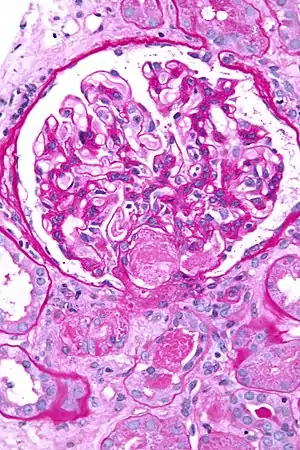

| Micrograph showing acute thrombotic microangiopathy due to DIC in a kidney biopsy. A clot is present in the hilum of the glomerulus (center of image). | |